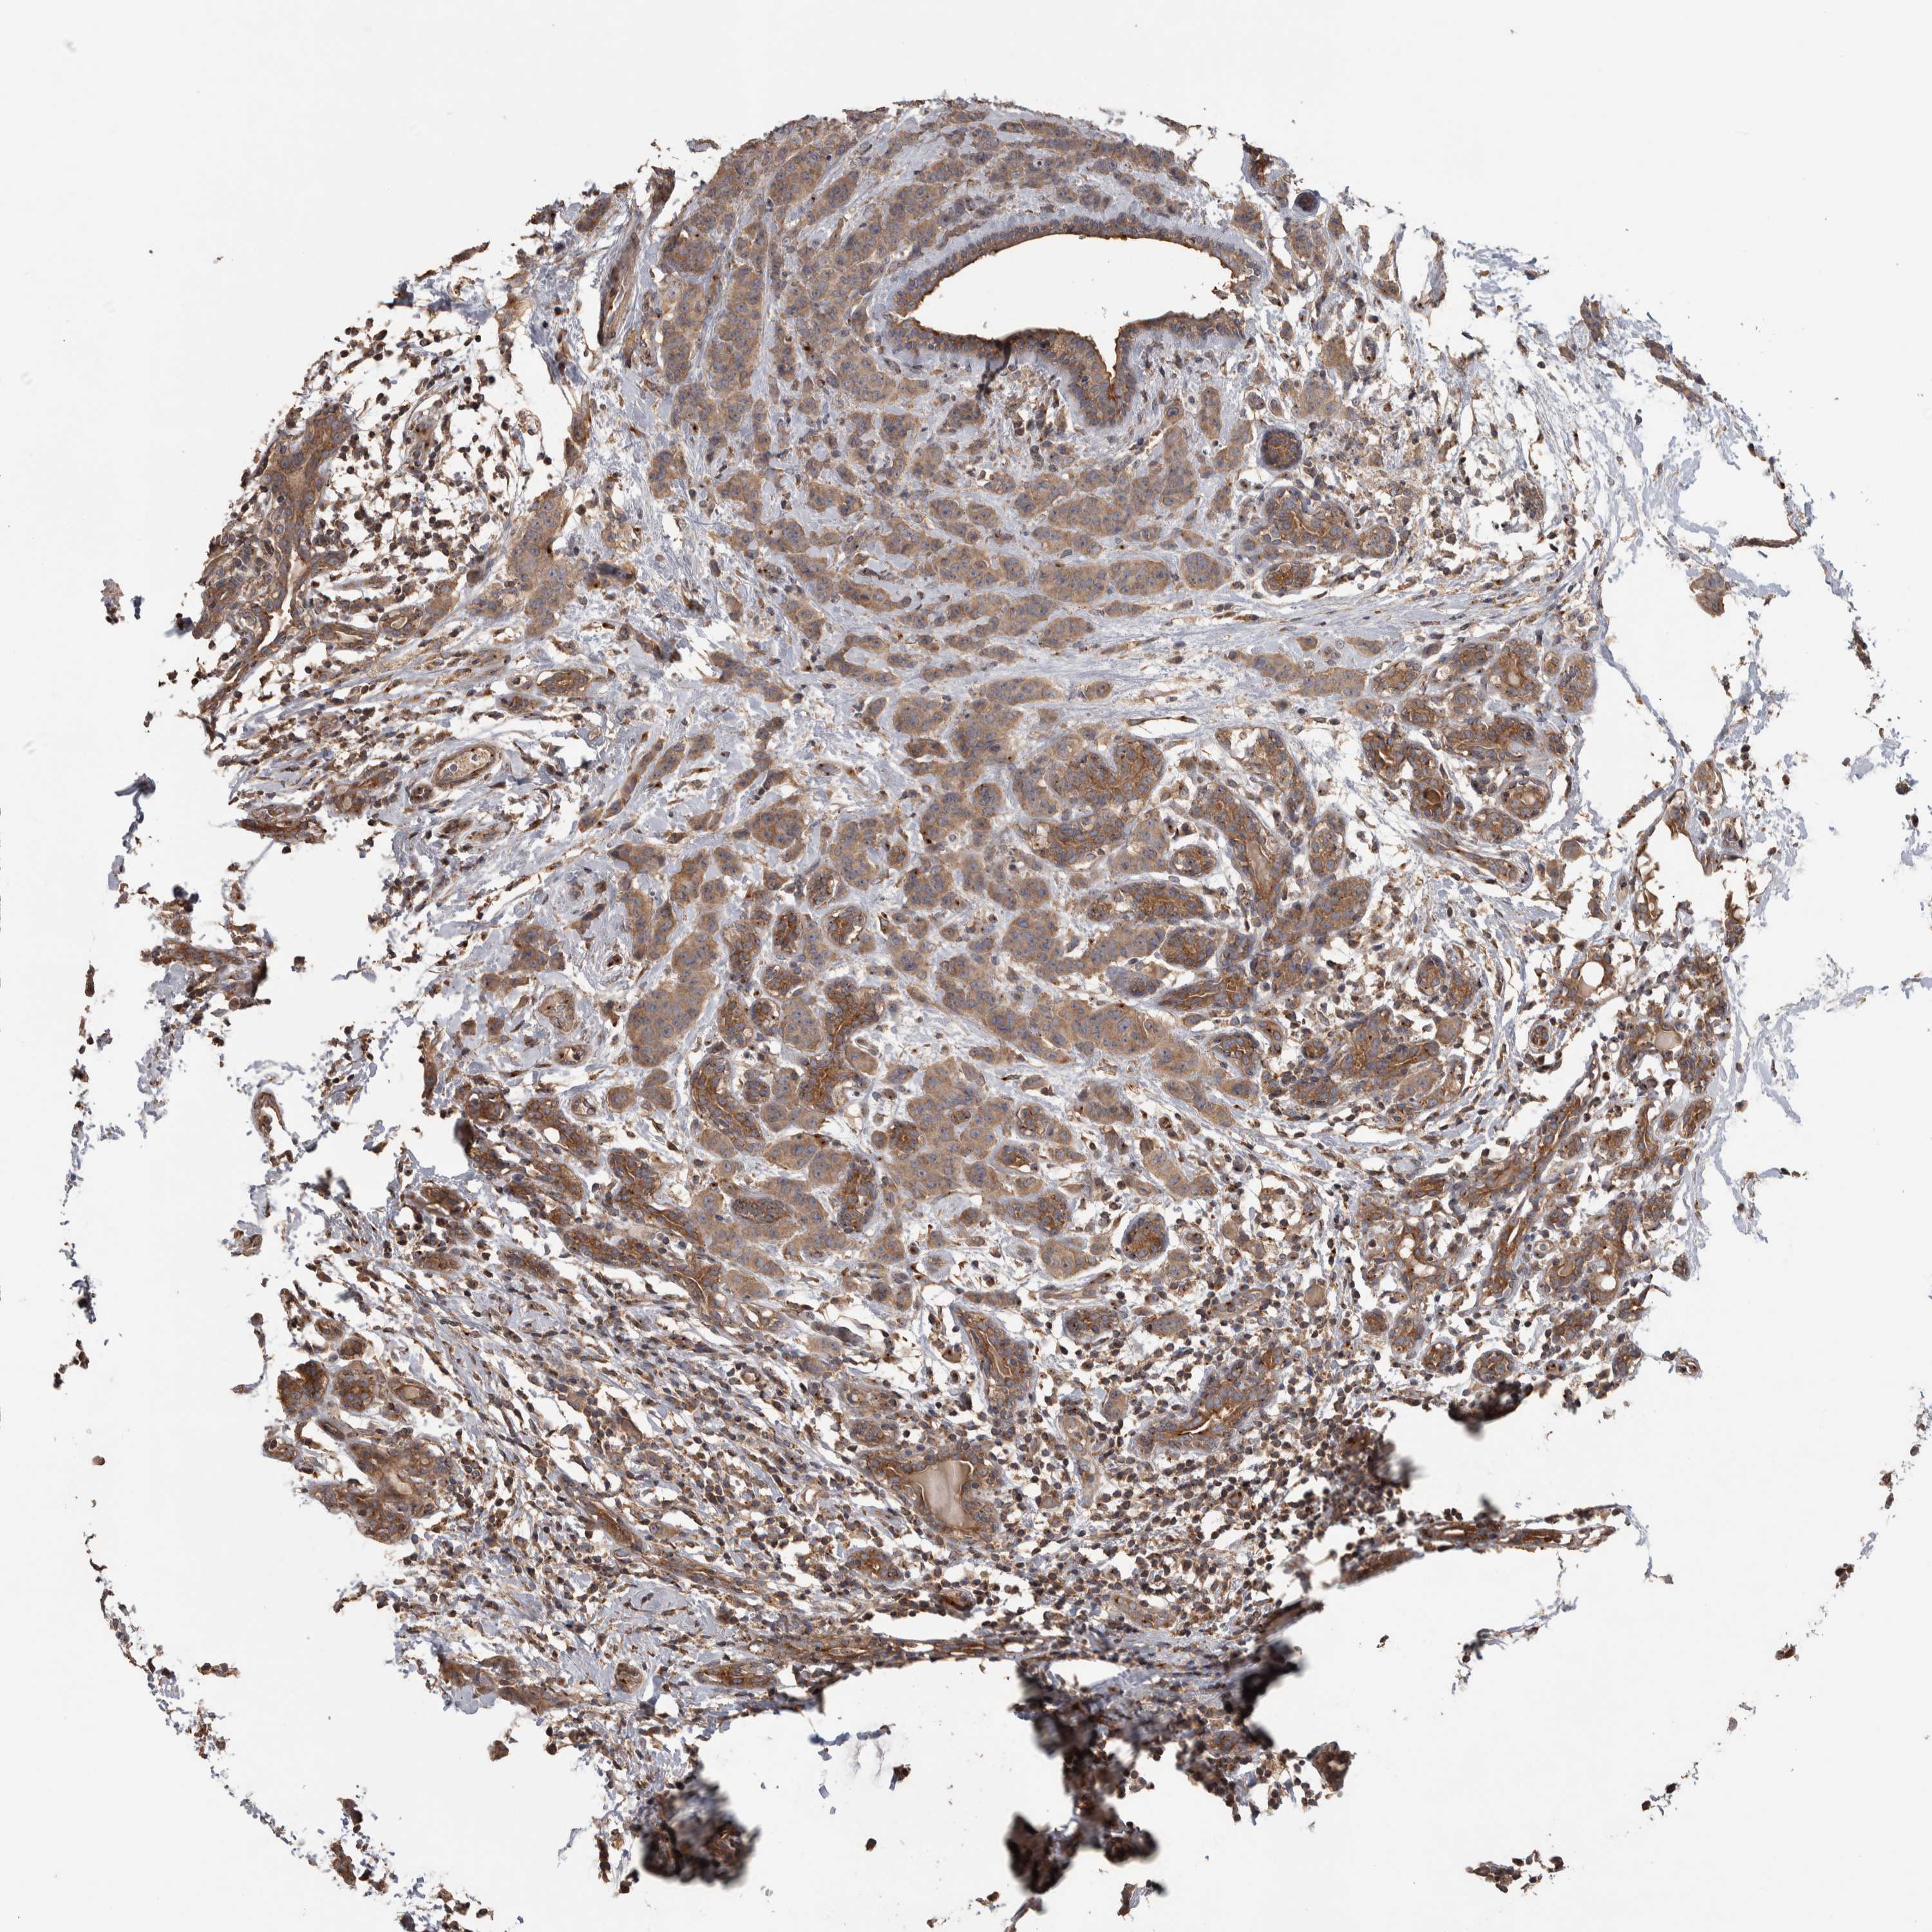

CANCER BREAST CANCER Show tissue menu

BRCA TCGA BRCA VALIDATION PROTEIN EXPRESSION